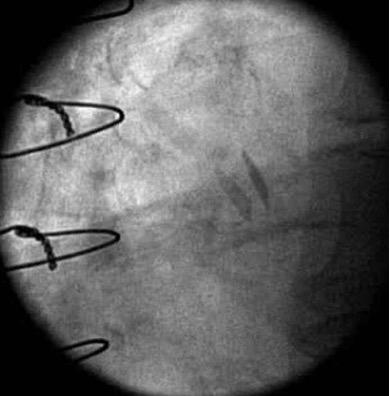

Mechanical valves have three basic types that have historically been used in clinical practice, and even without prior knowledge regarding the mechanical valve type, 2-D echo can usually lead to accurate identification of the prosthesis type. The bileaflet valve SJM Regent Mechanical Heart Valve (acquired by Abbott, Santa Clara, CA, USA) is the most commonly implanted mechanical prosthesis in the world [9, 10]. These valves consist of two semicircular disks with a narrow orifice along the center between the two disks and two larger lateral semicircular orifices. The disks open 75–90 degrees relative to the annular plane, and are easily identified with 2-D echo given the significant acoustic shadowing that results (Fig. 1). However, the degree of disc motion and opening is not always identifiable by 2-D echo. The degree of opening of bileaflet prostheses is better evaluated in the mitral position, as it can be identified in 77% and 100% of patients with TTE and TEE respectively. This drops to 13 and 35% respectively in the aortic position [11]. This has substantial significance to the specificity of 2-D echo in identifying complete opening of a leaflet prosthesis. The motion should be brisk and essentially consistent with each beat, though there may be intermittent changes in transprosthetic gradients that lead to variation in the degree of opening, and therefore conclusions should be drawn only after examination of several consecutive beats.

Fig. 1.Maximal opening of a 21 mm SJM Regent Mechanical Heart Valve in the aortic position with normal valve function. Fluoroscopy demonstrated brisk and complete opening and closing of the leaflets. Note the leaflets are not quite 90 degrees perpendicular to the annular plane at the time of maximal opening which still is within normal limits.